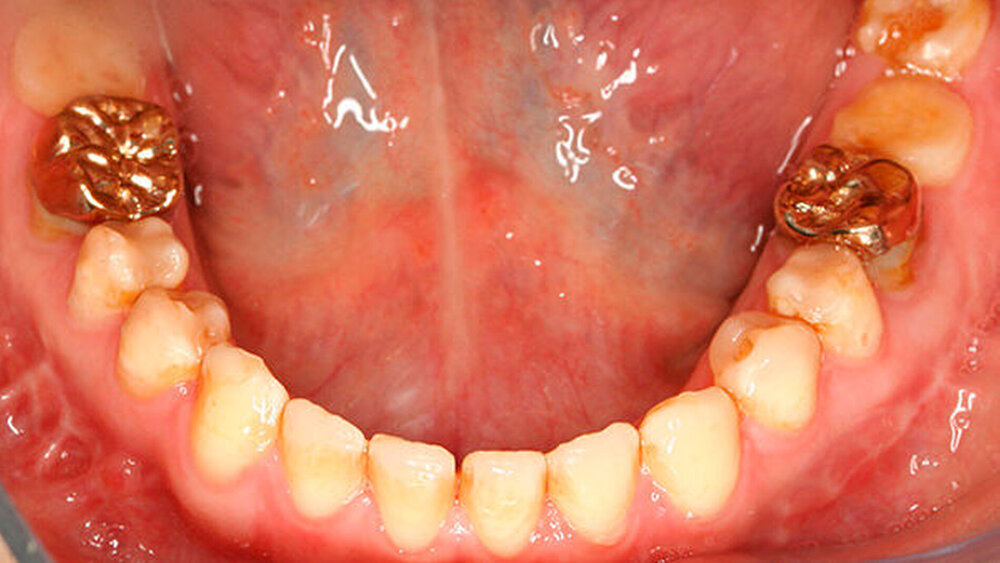

Bisher war die Patientin größtenteils mit provisorischen Maßnahmen behandelt worden. Eine Ausnahme bildeten hier die Sechsjahrmolaren, die ihrzufolge sehr zeitnah nach vollständigem Durchbruch mit Goldteil- beziehungsweise -vollkronen versorgt wurden. Im Oberkiefer wurden später auch für die zweiten bleibenden Molaren Vollkronen gewählt (Abbildungen 1 und 2).

Abbildung 1 gibt einen guten Überblick darüber, dass teils mehrere Restaurationen pro Zahn durchgeführt wurden und die dazwischen verbliebenen Bereiche aus Zahnschmelz oft nur gering waren (insbesondere an den Frontzähnen). Gleichzeitig zeigt aber auch der Vergleich der kontralateralen Prämolaren, wie anfällig dieser verbliebene Schmelz für Abplatzungen war. Im Unterkiefer ist gerade an Zahn 37 deutlich zu erkennen, wie großflächig die Schmelzverluste sein können, wenn auch die Restauration nicht mehr intakt oder vorhanden ist.